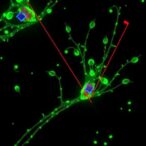

The concept is revolutionary: cancer cells exhibit a heightened metabolic demand and disrupted iron metabolism which causes them to uptake gallium ions preferentially. Once inside the malignant cells, gallium exerts cytotoxic effects, inducing apoptosis and halting tumor proliferation. Aston University’s team, led by Professor Richard Martin and Dr. Eirini Theodosiou, has demonstrated through rigorous laboratory tests that this gallium-doped bioglass achieves approximately 99% cancer cell kill rates in vitro, an unparalleled success that underscores the potential of this therapeutic modality.

The scientific underpinnings of the gallium-bioactive glass system rely heavily on the interplay of material science and cellular biology. The bioactive glass matrix acts as a scaffold releasing therapeutic gallium ions while its degradation products enhance bone remodeling processes. The gallium’s role is twofold: firstly, disrupting cellular mechanisms crucial for iron acquisition and metabolic activity in tumor cells, and secondly, promoting direct DNA damage leading to programmed cell death. This multifaceted mechanism leverages the unique vulnerabilities of cancer metabolism while preserving healthy osteoblast activity.

Early laboratory data have ignited optimism by demonstrating not only substantial destruction of cancerous cells but also measurable promotion of bone regeneration, which is critical in the context of metastatic bone lesions commonly seen in cancers such as breast and prostate. Regenerating bone within previously tumor-burdened areas could revolutionize rehabilitation and functional outcomes for patients suffering from both primary and metastatic bone malignancies.